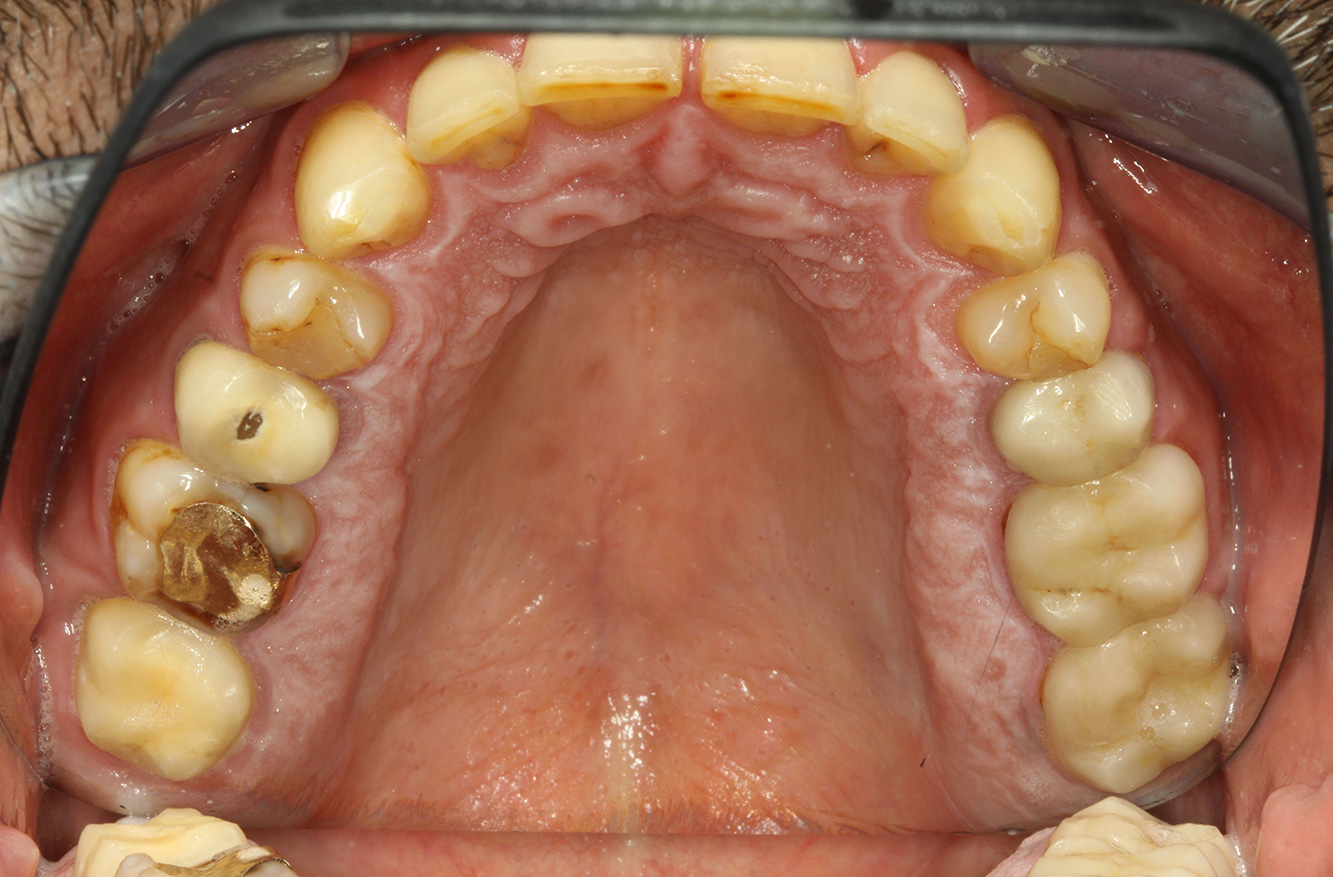

Il paziente ha 39 anni e in passato è stato sottoposto ad un intervento per la sostituzione della valvola aortica dovuta a insufficienza valvolare ed endocardite. Assume regolarmente l'ASS 100 come anticoagulante. Per quel che riguarda lo stile di vita, il regime alimentare seguito dal paziente è classificato come “dieta che favorisce la formazione della carie”, per via del consumo regolare di cibi ad alto contenuto di zuccheri e dei sei-sette pasti consumati al giorno. La salute orale del paziente indica un rischio moderato di carie, con lesioni attive. Il rischio di parodontite è basso, tuttavia il paziente è affetto da gengivite. Si formulano quindi i seguenti consigli per il trattamento di profilassi.

La sostituzione della valvola cardiaca e l'anamnesi di endocardite indicano un rischio aumentato di complicazioni. Al fine di ridurre il rischio di una nuova infiammazione, si deve consigliare una profilassi antibiotica (ad es. 2 g di amoxicillina un'ora prima della seduta). Nonostante la cura a lungo termine con un anticoagulante, non ci si aspetta un rischio aumentato di sanguinamento durante la seduta di profilassi.

Si consiglia una fluorizzazione per stimolare ulteriormente la prevenzione della carie, prevenire in particolar modo nuove formazioni intorno ai margini del restauro e per sigillare le superfici radicolari. Entrambi i provvedimenti possono ridurre la sensibilità dei denti alla temperatura.